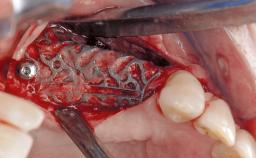

A 37-year-old male patient was referred to the Department of Periodontology at the University of Bern, Switzerland, by a private dentist. Tooth 21 had been lost due to trauma and had been replaced with an implant and a cemented single crown. The tapered-effect tissue-level implant had a diameter of 4.1 mm, a length of 12 mm, and a sandblasted and acid-etched (SLA) surface (Straumann Dental lmplant System; Institut Straumann AG, Basel, Switzerland). The metal-ceramic crown had been cemented permanently, leaving a submucosal gap between the implant shoulder and the crown margin. Absence of marginal bone loss apical to the polished transmucosal neck of the implant could be observed .